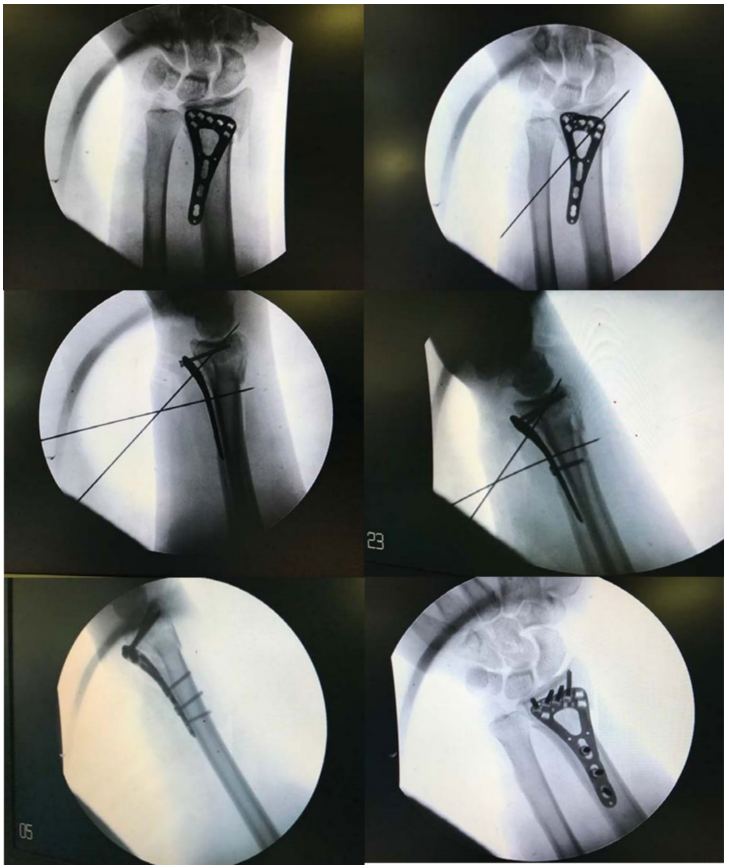

钢板定位在分水岭线近侧,通过尺侧瞄准导向器用1.8mm克氏针临时固定。用C型臂确认位置并进行调整,直至克氏针到达软骨下骨。通过外侧克氏针实现额外固定,随后放置螺钉(先远端螺钉,后骨干螺钉)。通过旋前方肌上的小戳口插入骨干螺钉。如果关节面碎片有塌陷,可通过钢板窗口使用克氏针进行复位(图2)。在关节外骨折中,通过活动腕关节并将骨骼固定到钢板上实现复位。依次插入并拧紧近端和远端螺钉完成最终固定(图1, 3)。使用皮下MONOCRYL 4-0缝线关闭皮肤。在本研究中,对于关节内和粉碎性骨折,使用KLS Martin可变角度锁定加压钢板桡骨远端钢板进行固定;对于简单的关节外骨折,使用SMPL桡骨远端T型板进行固定,两者均为钛合金材质。

图3 分步透视图像